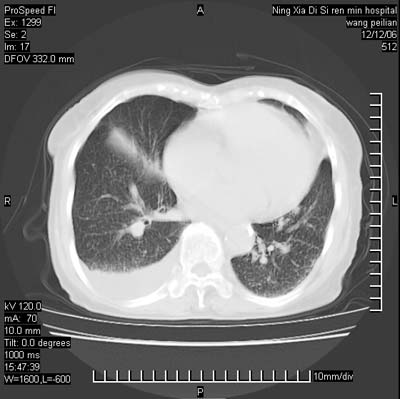

标题: CT5609:胸部:女77 病史不详

两肺可见多个大小不等的结节,左侧有胸水,纵隔淋巴结增大,考虑是细支气管肺泡癌

两肺尖纤维索状影,两下肺结节块状影,且有钙化灶,右胸腔积液。考虑肺结核并胸膜炎。

两肺尖纤维索状影,两下肺结节块状影,且有钙化灶,右胸腔积液。考虑肺结核并胸膜炎肺间质纤维化

考虑:1、慢性支气管炎合并全小叶型肺气肿、间质纤维化;

2、双肺结核;

3、右侧胸膜炎(积液)。

1、双肺继发型肺结核(以纤维、增殖灶为主);

2、右侧胸腔积液;

3、其余符合老年肺改变。

双肺见多个结节状及条索状影,双侧胸腔积液,右侧叶间积液,考虑结核性胸膜炎